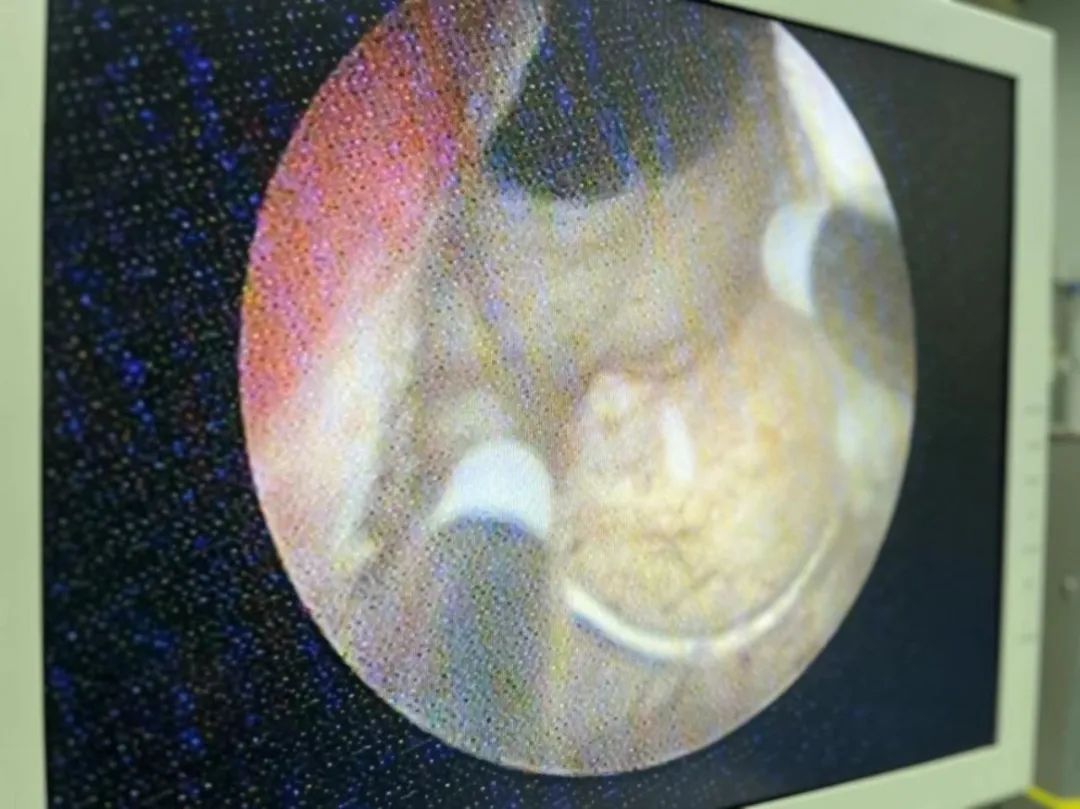

泌尿外科团队结合患者情况,决定采用“前列腺等离子电切术”进行治疗。这一手术具有创伤小、恢复快、并发症少等优点,是治疗前列腺增生症的“金标准”手术。

深圳永福医院泌尿外科龚红星主任表示,前列腺增生是中老年男性常见的疾病之一,其症状严重影响患者的生活质量。前列腺等离子电切术作为一种微创手术,具有显著的治疗效果和较低的并发症发生率。目前,深圳永福医院常规开展前列腺等离子电切术,为广大患者提供更加优质、高效的医疗服务。